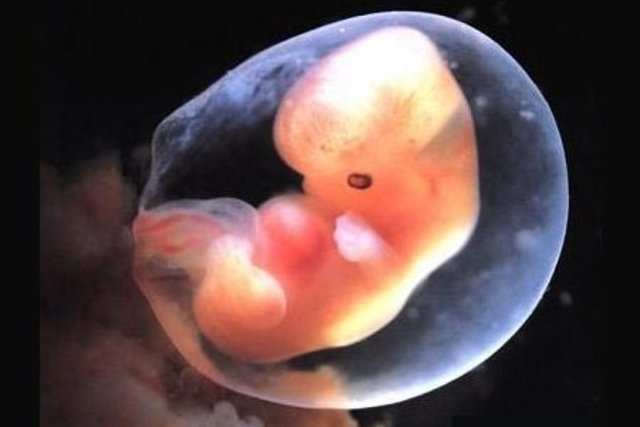

• Semanas 4 a 5

Semanas 4 a 5

Las yemas o brotes de brazos y piernas se vuelven visibles

El cerebro se desarrolla en 5 áreas y algunos nervios craneales son visibles

Comienza el desarrollo de las estructuras del ojo y del oído

Formación del tejido que se ha de convertir en las vértebras y algunos otros huesos

Desarrollo posterior del corazón que ahora late a un ritmo regular

Movimiento de sangre rudimentaria a través de los vasos mayores

• Semana 6

Semana 6

Los brazos y las piernas se han alargado y se pueden distinguir las áreas de los pies y de las manos

Las manos y los pies tienen dedos (dígitos), pero pueden aún estar adheridos por membranas

El cerebro continúa formándose

Comienza la formación de los pulmones

• Semana 7

Semana 7

Se forman los pezones y folículos pilosos

Los codos y los dedos de los pies son visibles

Todos los órganos esenciales se han comenzado a forma

• Semana 8

Semana 8

Los párpados están más desarrollados

Las características externas del oído comienzan a tomar su forma final.

Continúa el desarrollo de las características faciales

Los intestinos rotan.